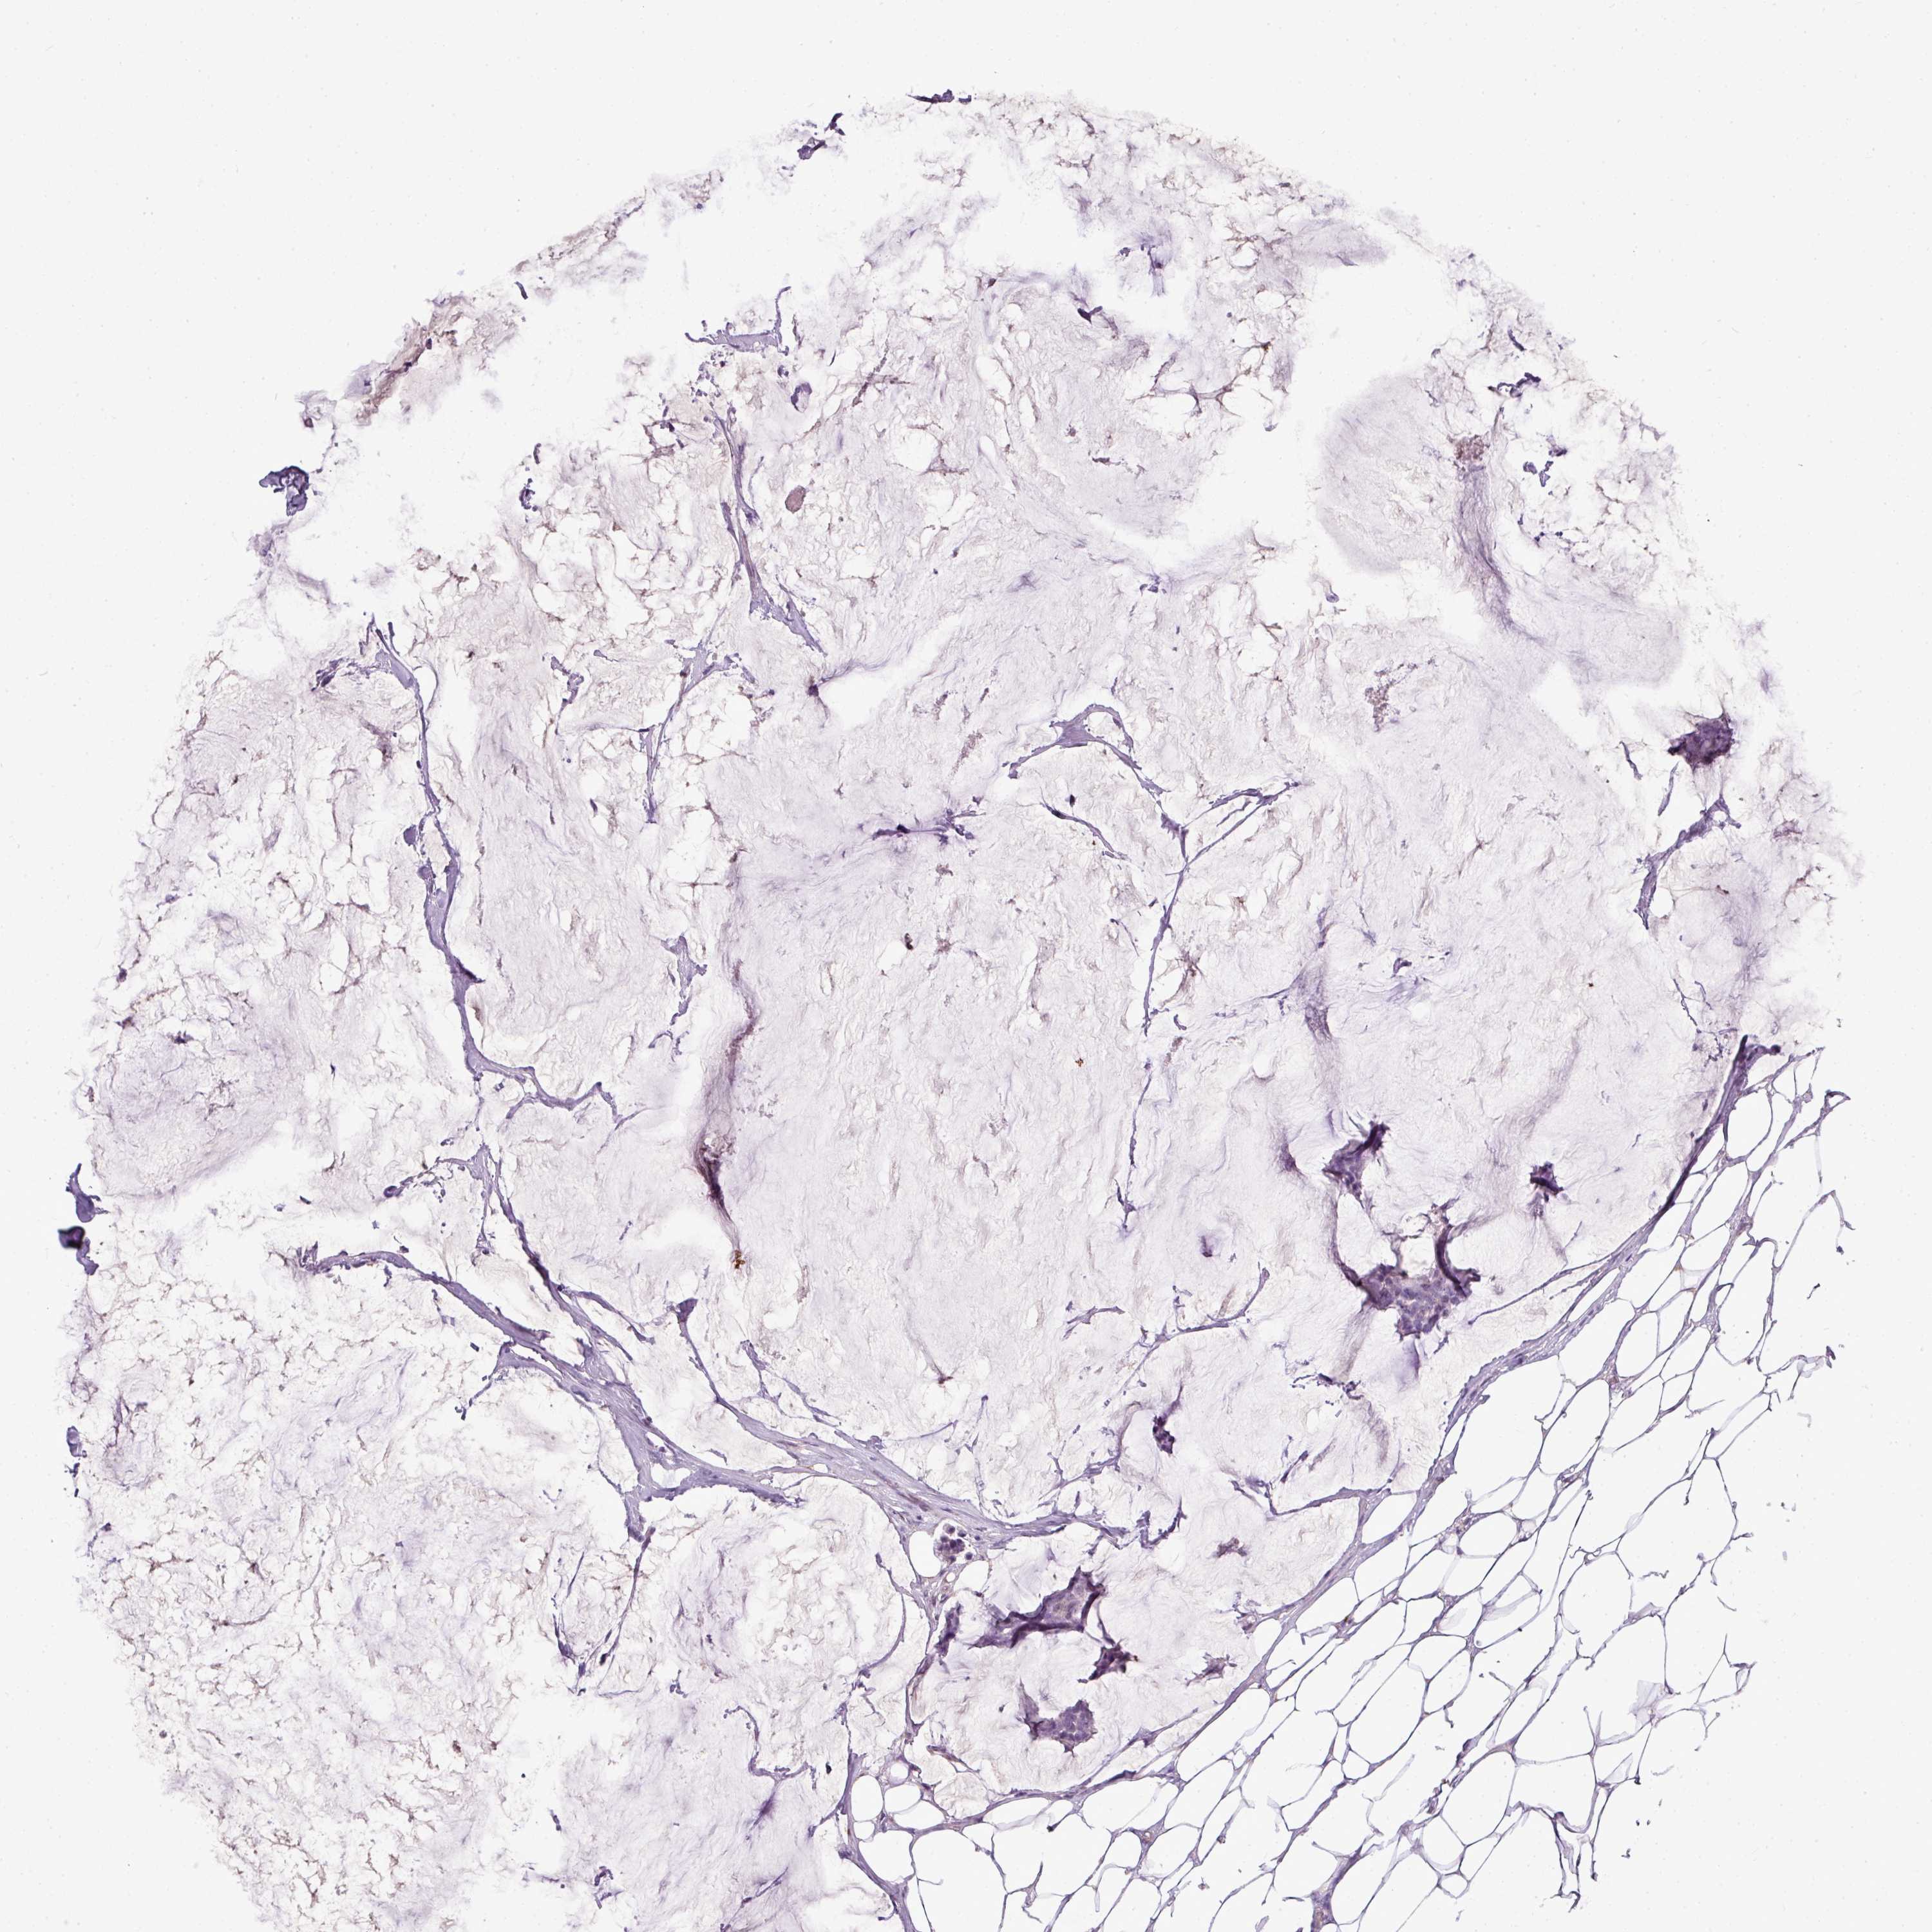

CANCER BREAST CANCER Show tissue menu

BRCA TCGA BRCA VALIDATION PROTEIN EXPRESSION